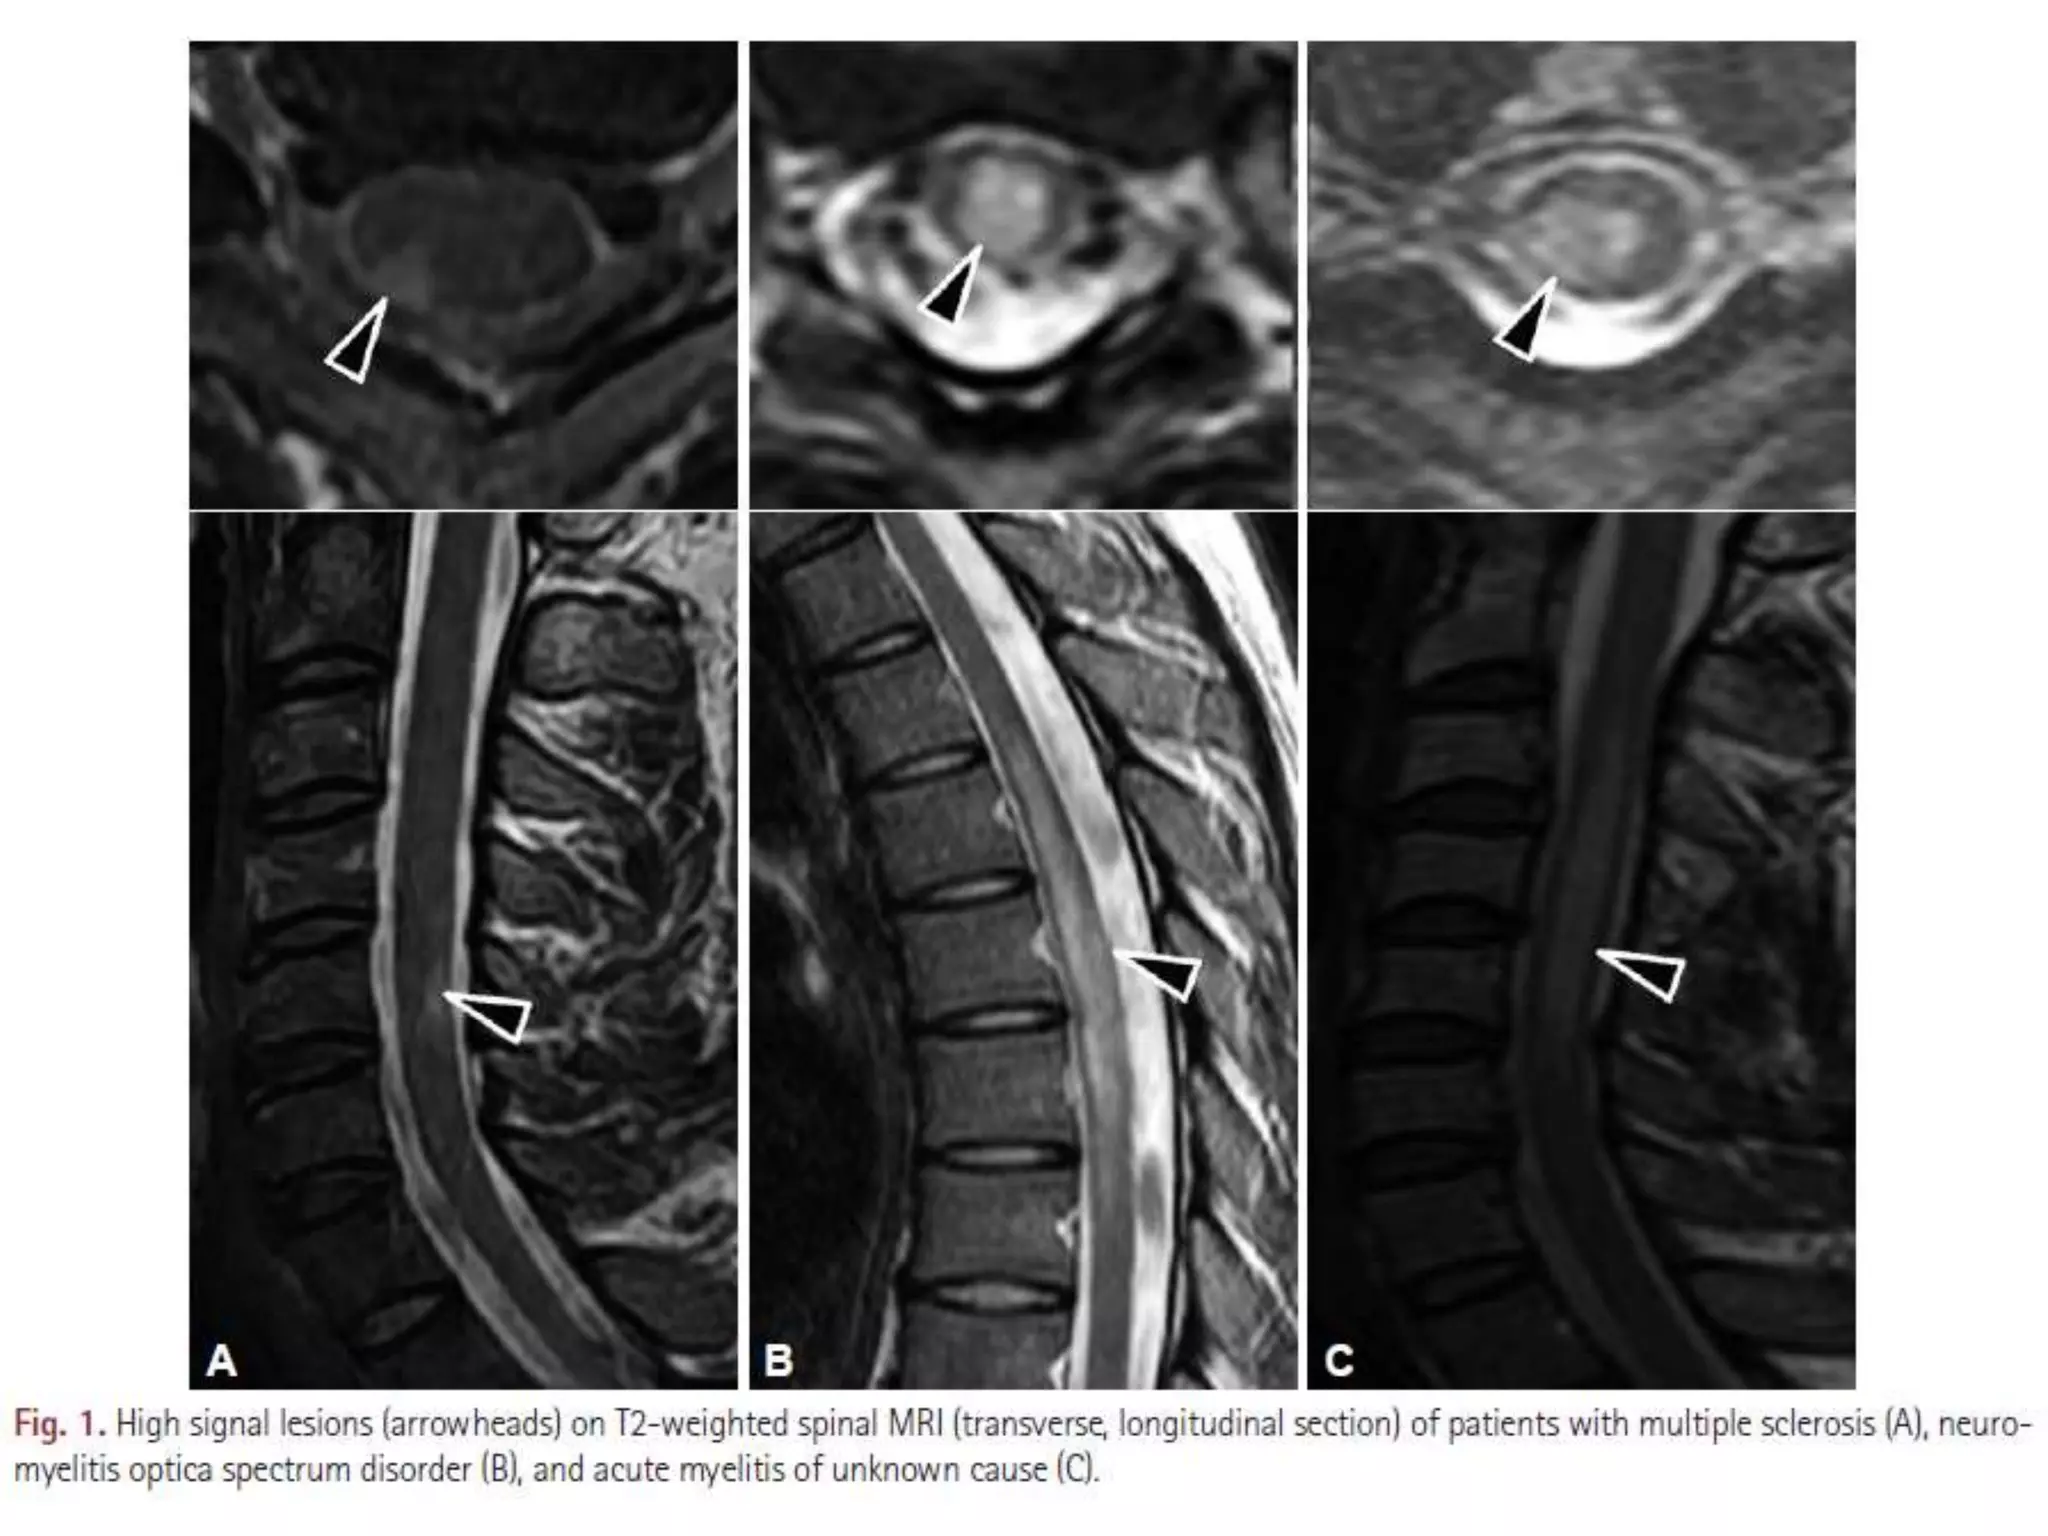

• MRI spinal memperlihatkan variasi panjang lesi (berkisar dari

satu sampai delapan segmen vertebrae), dan juga ditemukan

METODE Pasien mielitis akut dengankeluhan awal hanya gejala sensorik. Datang ke Ewha Womans University Medical Center (EUMC) Januari 1999 – September 2006 dan National Cancer Center (NCC) September 2005 – April 2014 Gejala positif Nyeri neuropatik, hiperalgesia, alodinia, dan parestesia. Gejala negatif Hipoestesia dan baal. KRITERIA INKLUSI - Hanya mengeluh gejala sensorik dalam 3 minggu pertama. - Pada MRI spinal menunjukkan sinyal T2 kuat. KRITERIA EKSKLUSI Terdapat disfungsi motorik atau otonom. 7 Rekam medis, data laboratorium, dan gambaran MRI ditinjau dan dianalisis secara retrospektif.